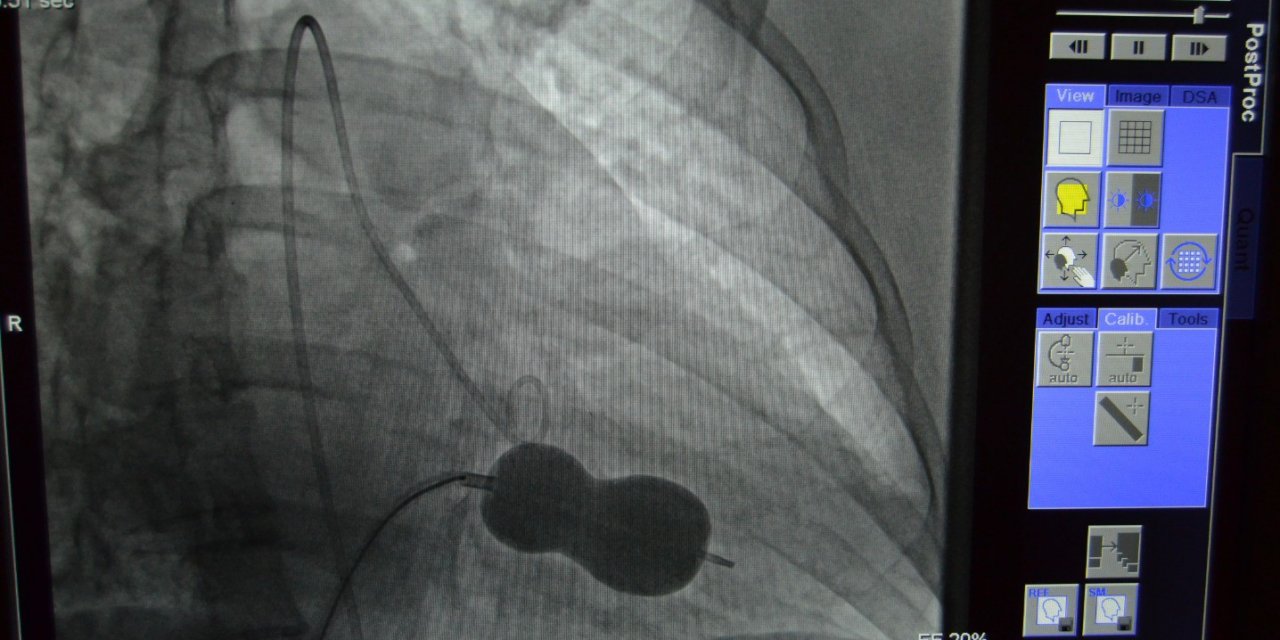

Niğde’de Ortopediye Teknolojik Güç: 4 Yeni Artroskopi Cihazı Hizmete Girdi